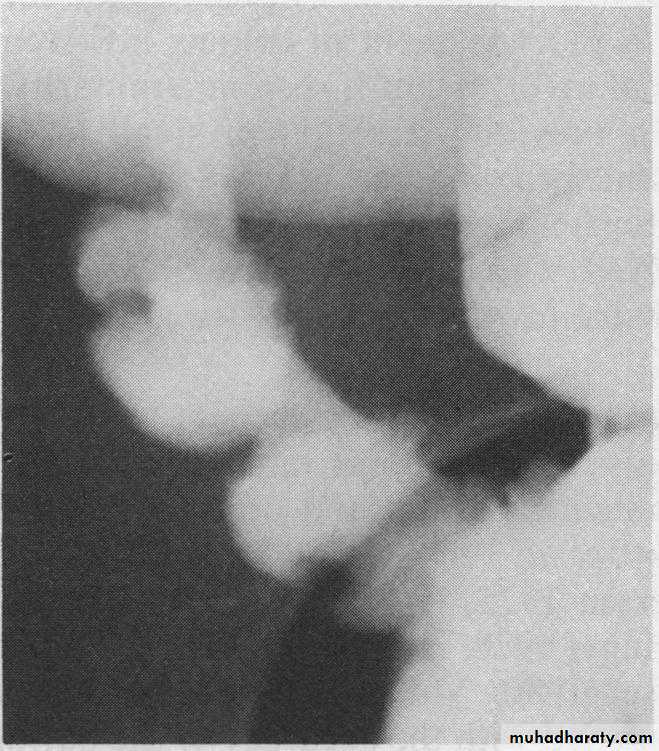

X-Ray Manifestations

• Squaring of the folds-early manifestation from obstructive lymphedema• Apthous ulcers-small nodular filling defects (mound of edema) with central ulceration

• Skip lesions-discontinuous involvement of the bowel with intervening normal areas

• Cobblestoning-irregular, blanket-like appearance to bowel wall caused by criss-crossing longitudinal and transverse ulcers separated by areas of edema

• Pseudopolyps-islands of hyperplastic mucosa between denuded areas of mucosa

• Filiform post-inflammatory polyps

• Pseudodiverticula-from bulging area of normal wall opposite side of scarring from disease, usually on anti-mesenteric side

• String-sign-marked narrowing of terminal ileum (usually) from a combination of edema, spasm and (sometimes, but not always) fibrosis; frequently associated with proximal dilatation